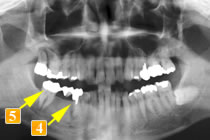

47歳男性

初診時、左下奥から3番目の歯(

)は、根に膿の袋ができており、歯が割れている可能性がありました。

この時点で抜歯の可能性が高いケースでした。

しかし

は何とか残したいということで“再植術”を行いました(

)。

(抜いて根の治療をした後に再度植えました。)

は初診時同様ブリッジとして使うには負担が大きすぎてすぐダメになってしまうと判断し、この歯を何とか残すために歯のない部分はインプラントという治療法を選択しました(

)。これならつながないでいいですし、インプラントでも噛む力が負担できるので他の歯を守れます。

さらに、

に関しても抜歯適応と思われましたが、何とか残すため“再植術”を行いました。